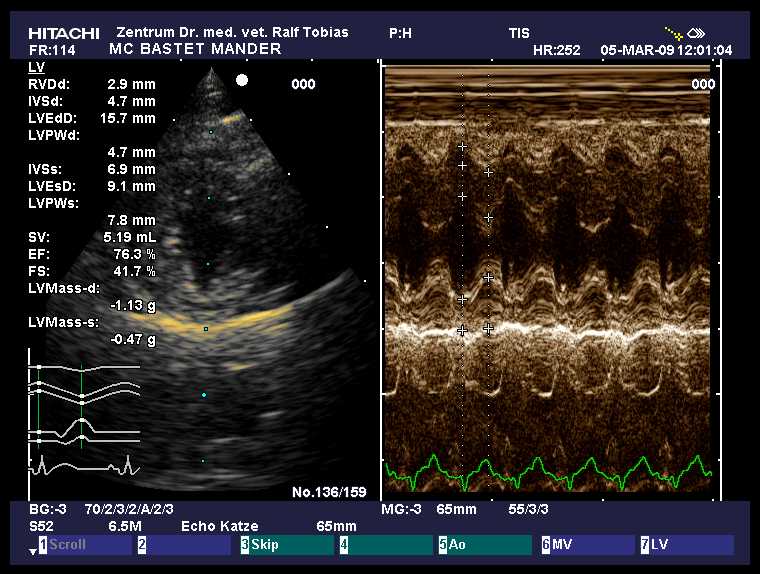

HCM-Schall März 2009

|

HCM normal

other diagnosis:

ggr. Mitralklappeninsuffizienz

age: 5y 2m

weight: 5.0 kg

IVSd: 5.0 mm

LVFWd: 4.7 mm

SAM: no

papillary muscles: normal

Dr.Tobias, Hannover